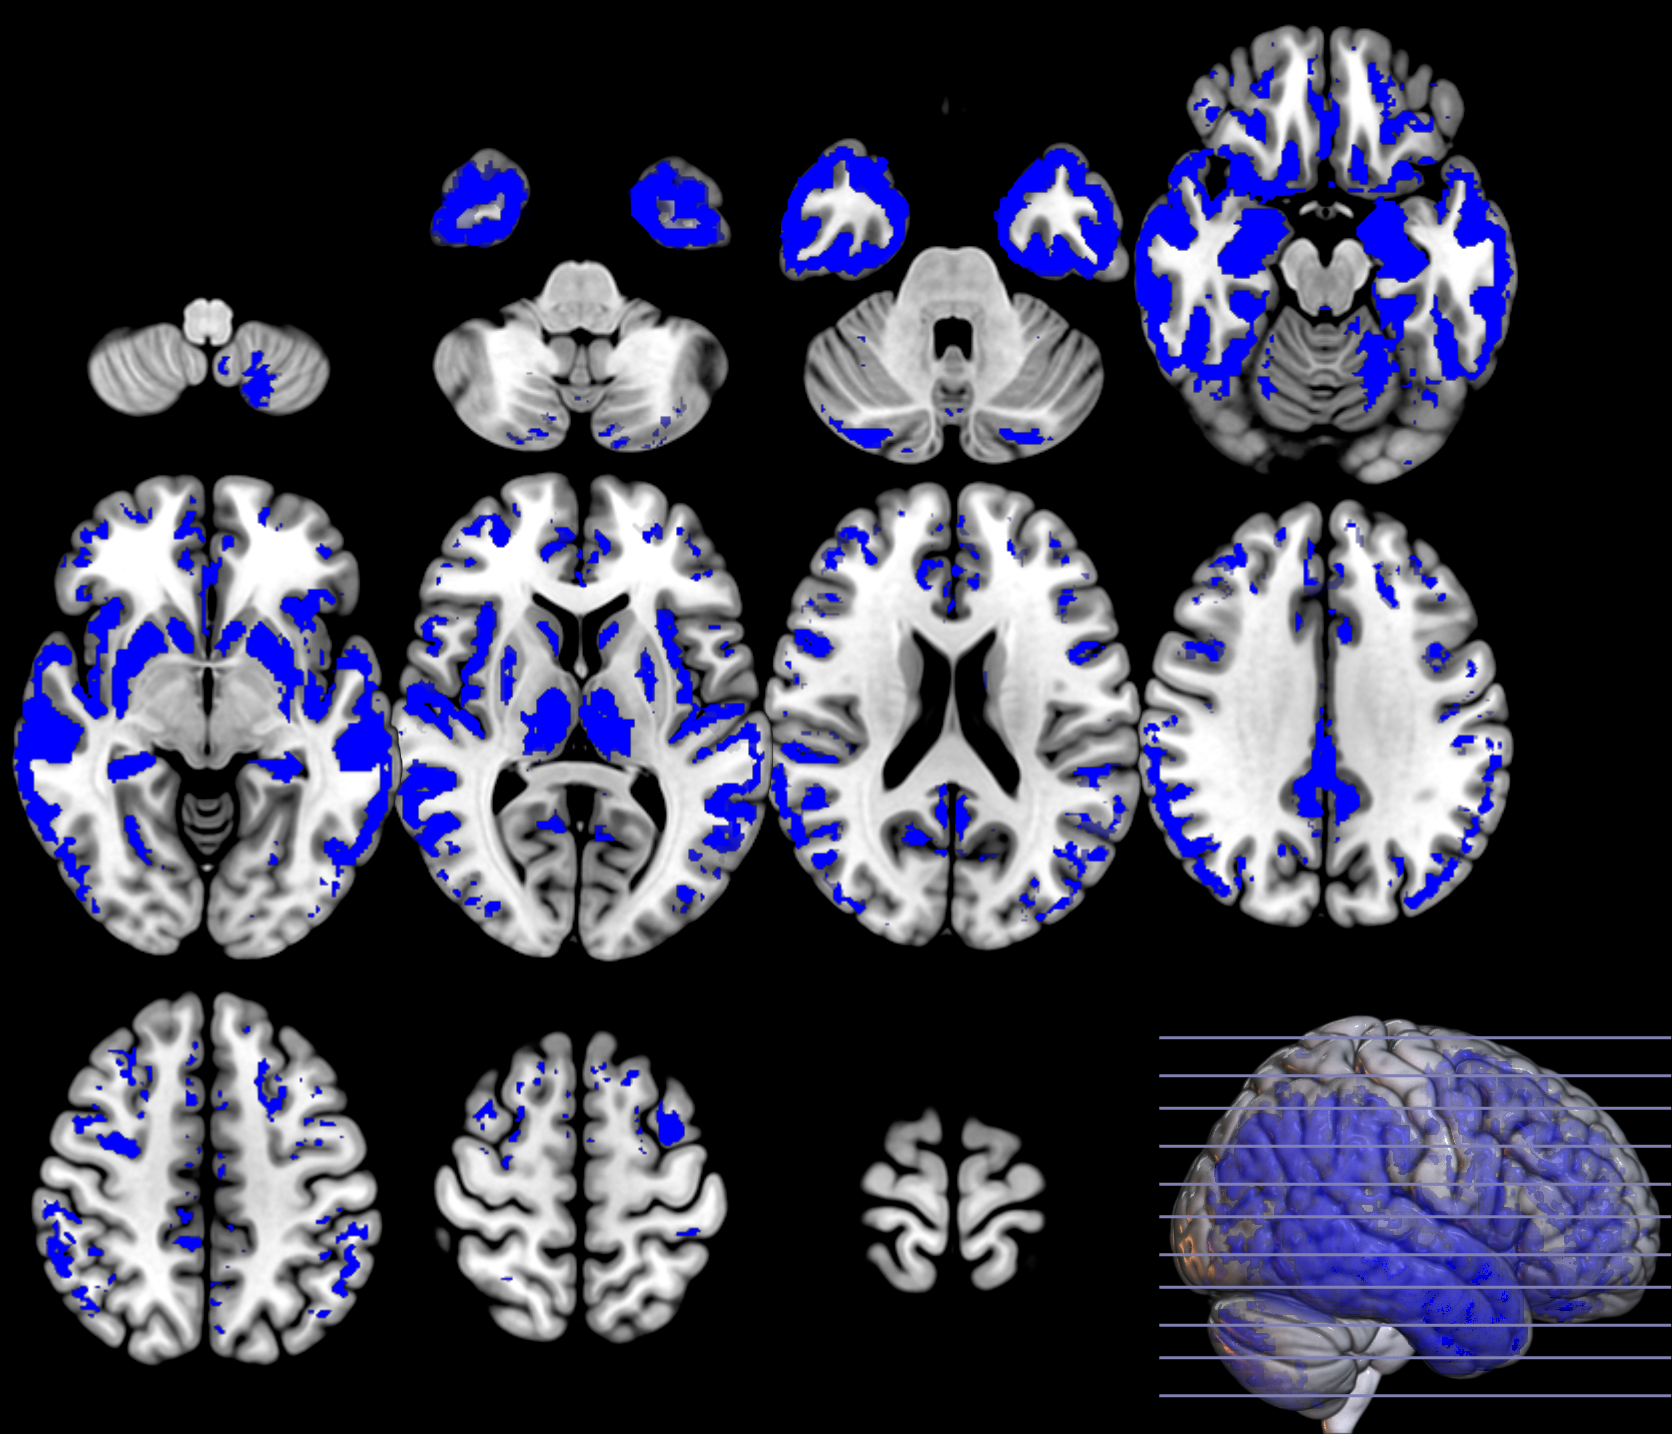

In the last part of this section, we show the inference analysis derived from the two methodologies on each domain. We regress on the observations and on the labels to construct and assess the spatially extended statistical processes, which provide maps of significance, using the MRI ADNI dataset [18]. In this way, we compare SPM, that is based on a two-sample T-statistic similar to equation 3, where significance is individually assessed at each voxel with a using three configurations: cluster-defining threshold CDT of (uncorrected for multiple comparisons), cluster extent threshold equal to and FWE correction at , and the P-tests described in section 2.2.3.

Based on the and values from the original dataset, and the ones obtained using a permutation analysis () for a selection of structures, e.g. hippocampus, we can compare the SPM with the previous inference approaches, as described in section 2.2.3. Note that in this paper the huge amount of voxels contained within an image limits the permutation analysis in this sense to some specific structures. Results on the hipocampus are depicted in figure 13. The permutation analysis reveals how the power of the approach is affected in this featured region, where a real effect might be found in almost the whole structure. The statistical power of the is preserved through the permutation procedure ( detected voxels vs voxels as shown in the same figure). It is also worth mentioning the CDF of the errors derived in the specific region and the distribution of the p-values within it. Recall that the dataset include advanced AD subjects thus the selected structure should be clearly affected by the disease.

To preliminary extend the analysis to the whole volume we approximately simulate the null distribution outside this featured region in two steps. First, we compute the set of p-values in the hippocampus (around voxels) following equation 16 and determine the T threshold that approximately provides the significance level, e.g. . Then, assuming that for any the probability of observation is , we threshold the rest of the image to obtain the significant voxels showing an effect. This approach clearly needs the multiple-comparison correction as several dependent or independent statistical tests are being performed simultaneously at the given significance level. Therefore, we decrease the significance level down to to avoid the presence of false positives in permutation analyses and then compare with SPM in the whole volume using the aforementioned configurations. In figure 13 we show the detection ability together with the control of type I error in the approach (map in red font). Note how the permutation test affects the detection ability of the classical CV approach (map in green font) and how the uncorrected voxelwise SPM approaches (in blue font ) tends to inflate false positives.